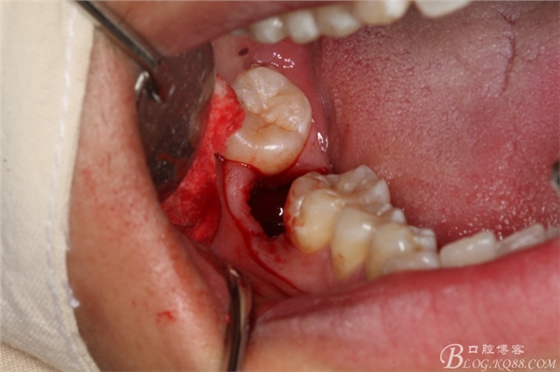

圖15.梃子放頰側(cè),以頰側(cè)骨板做支點(diǎn)。挺松47牙根。

圖16.挺出47牙根

圖17.持針器牽引出47牙根

圖18.牙根取出后,牙槽窩形狀未改變